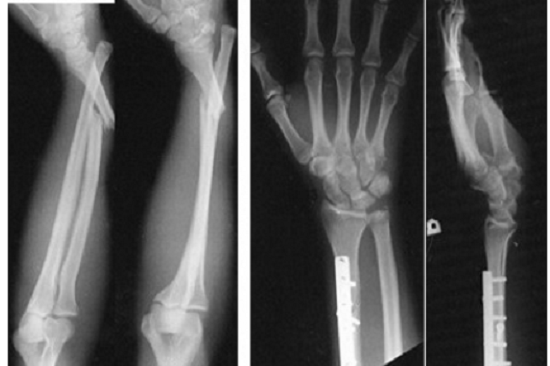

Click vào ảnh để xem 4 hình ảnh minh họa

Chụp X-quang. Sử dụng tia bức xạ thấp, X-quang là một liệu pháp tốt để thấy xương. X-quang không làm bạn đau và chỉ mất vài phút để hoàn thành;

Phẫu thuật và các thủ thuật khác. Nếu không cố định được bằng bột hay nẹp, bạn có thể cần phẫu thuật để cấy ghép thiết bị cố định bên trong chẳng hạn như đĩa, thanh hoặc đinh vít, hoặc ghép xương để duy trì vị trí thích hợp của xương trong quá trình lành thương.